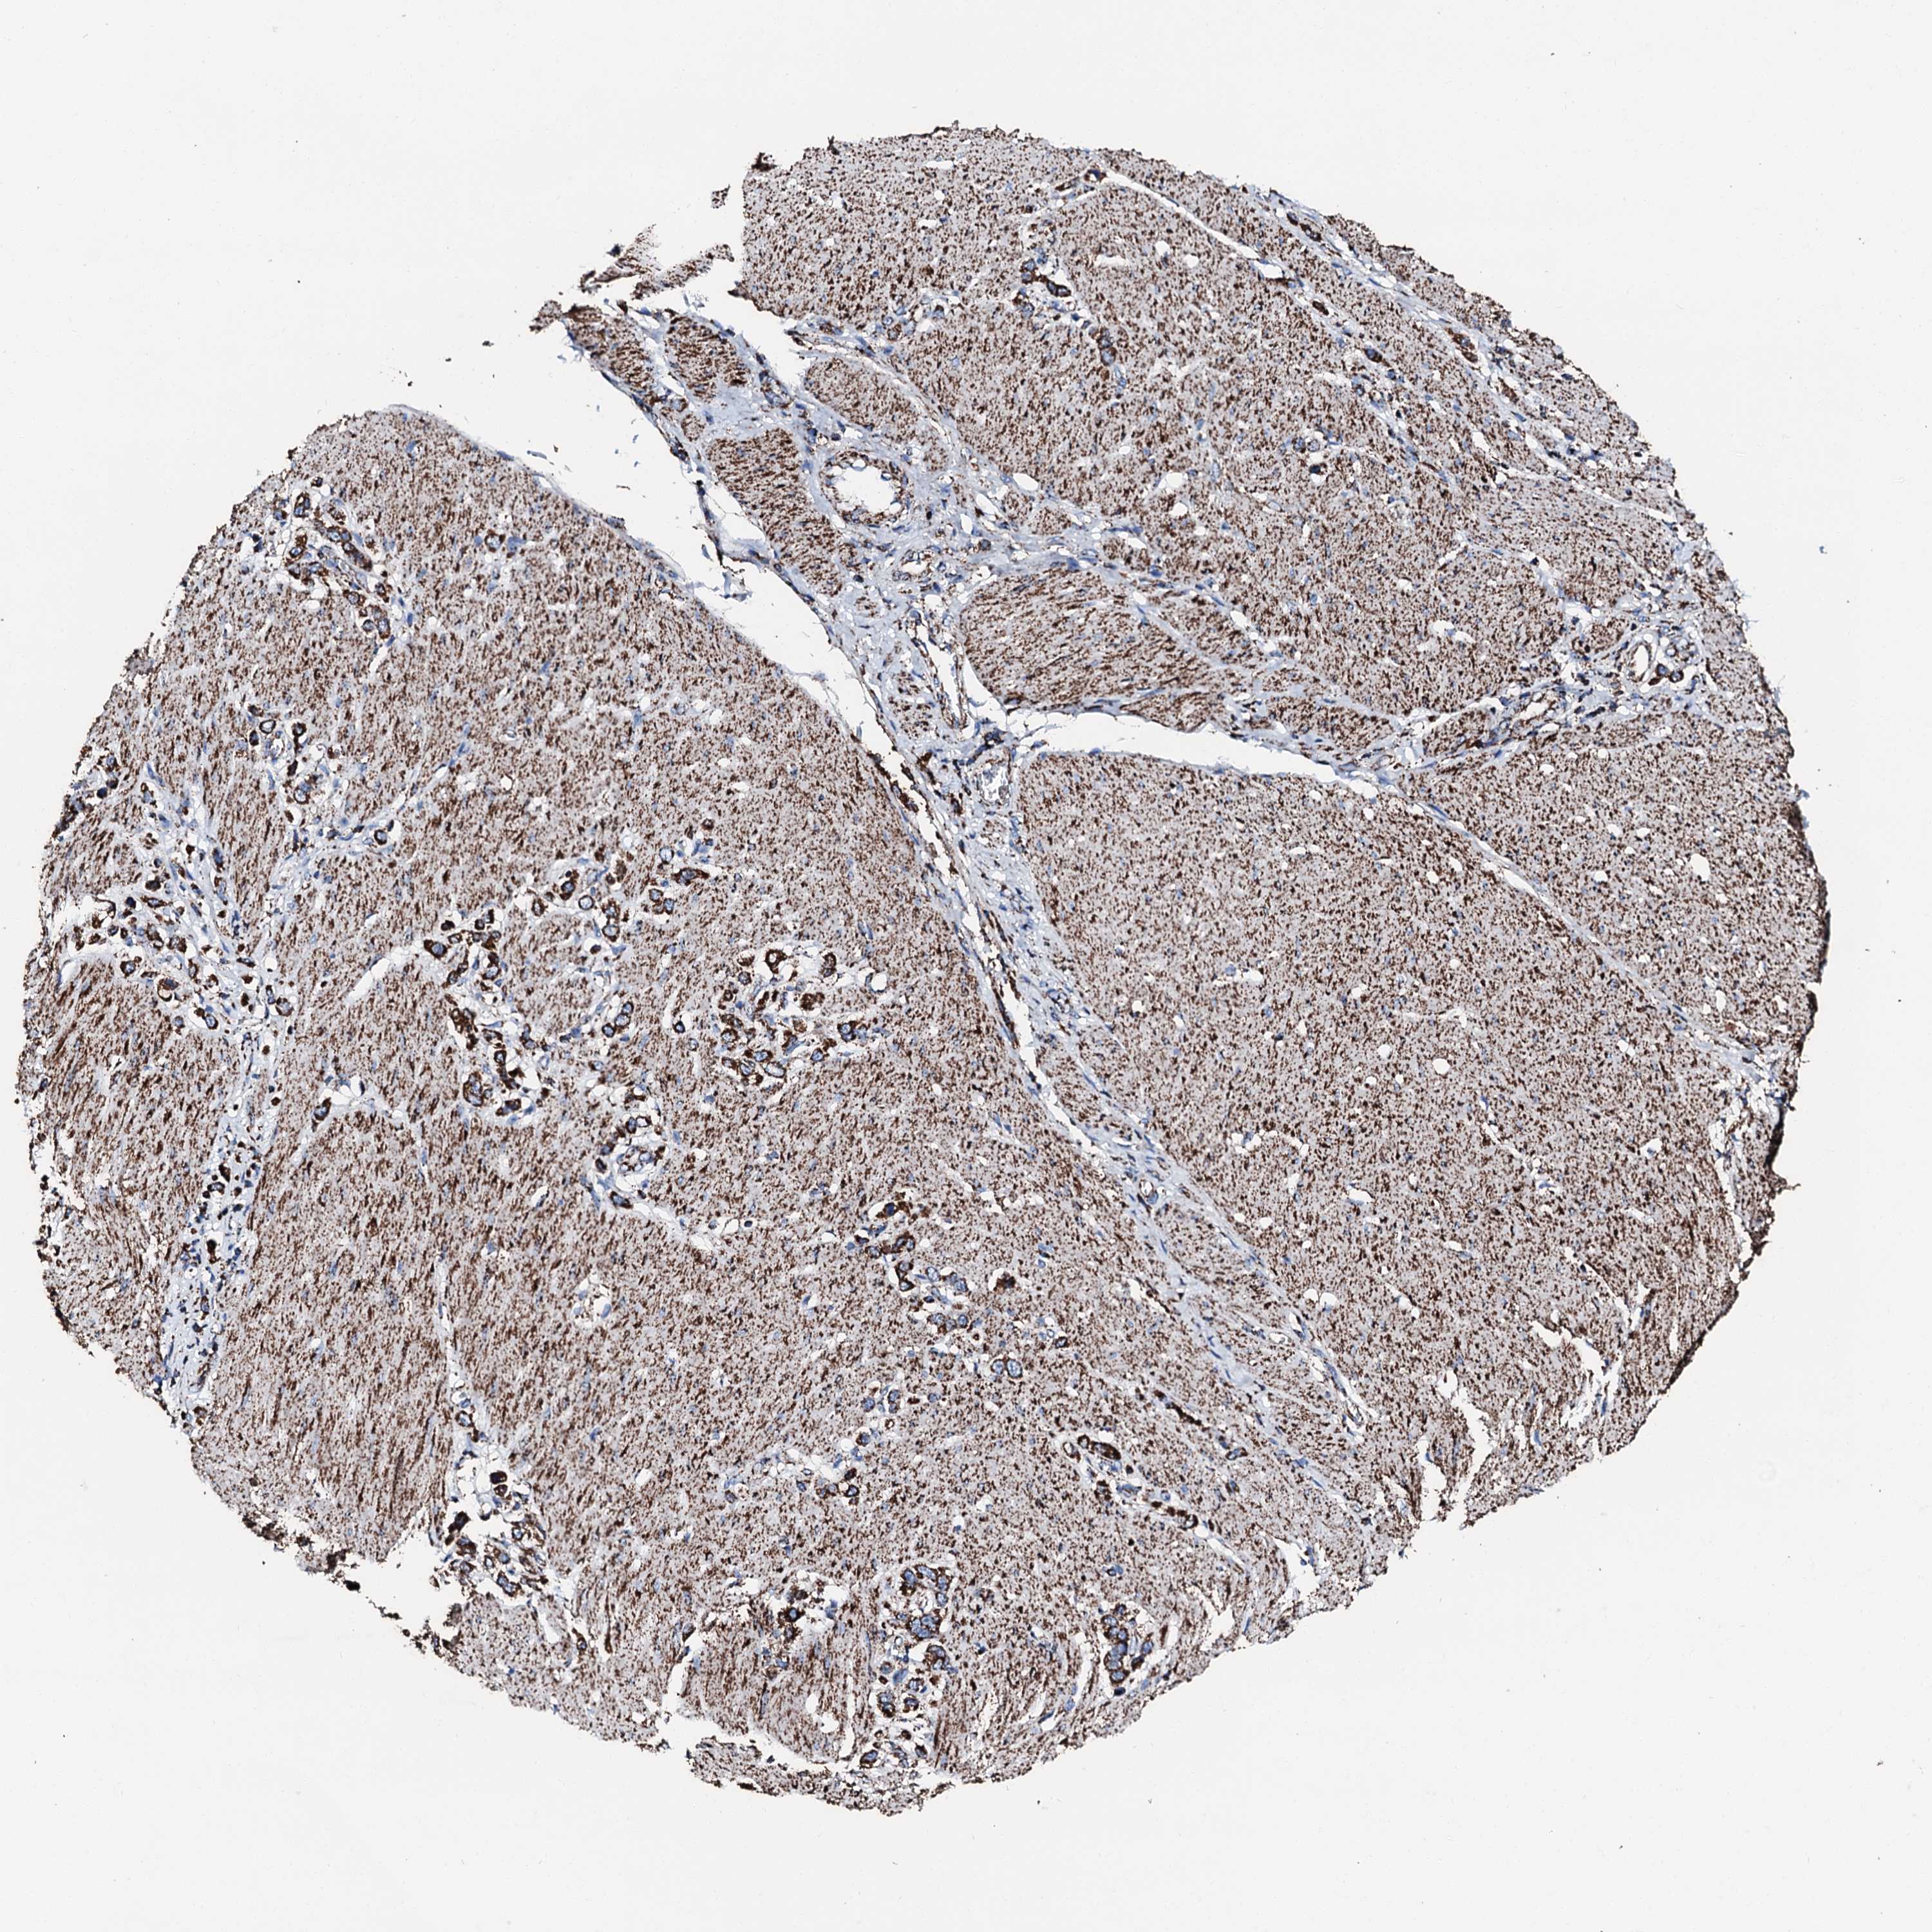

STOMACH CANCER - Protein expressioni

A mouse-over function shows sample information and annotation data. Click on an image to view it in a full screen mode. Samples can be filtered based on level of antibody staining by selecting one or several of the following categories: high, medium, low and not detected. The assay and annotation is described here.

Note that samples used for immunohistochemistry by the Human Protein Atlas do not correspond to samples in the TCGA dataset.

Antibody stainingi

Antibody staining in the annotated cell types in the current human tissue is reported as not detected, low, medium, or high, based on conventional immunohistochemistry profiling in selected tissues. This score is based on the combination of the staining intensity and fraction of stained cells.

Each image is clickable and will lead to virtual microscopy that enables deeper exploration of all samples and also displays staining intensity scores, fraction scores and subcellular localization as well as patient and tissue information for each sample.

Antibody HPA039588

Antibody HPA043888

Staining

High

Medium

Low

Not detected

Intensity

Strong

Moderate

Weak

Negative

Quantity

>75%

75%-25%

<25%

None

Location

Nuclear

Cytoplasmic/membranous

Cytoplasmic/membranous,nuclear

Adenocarcinoma, NOS